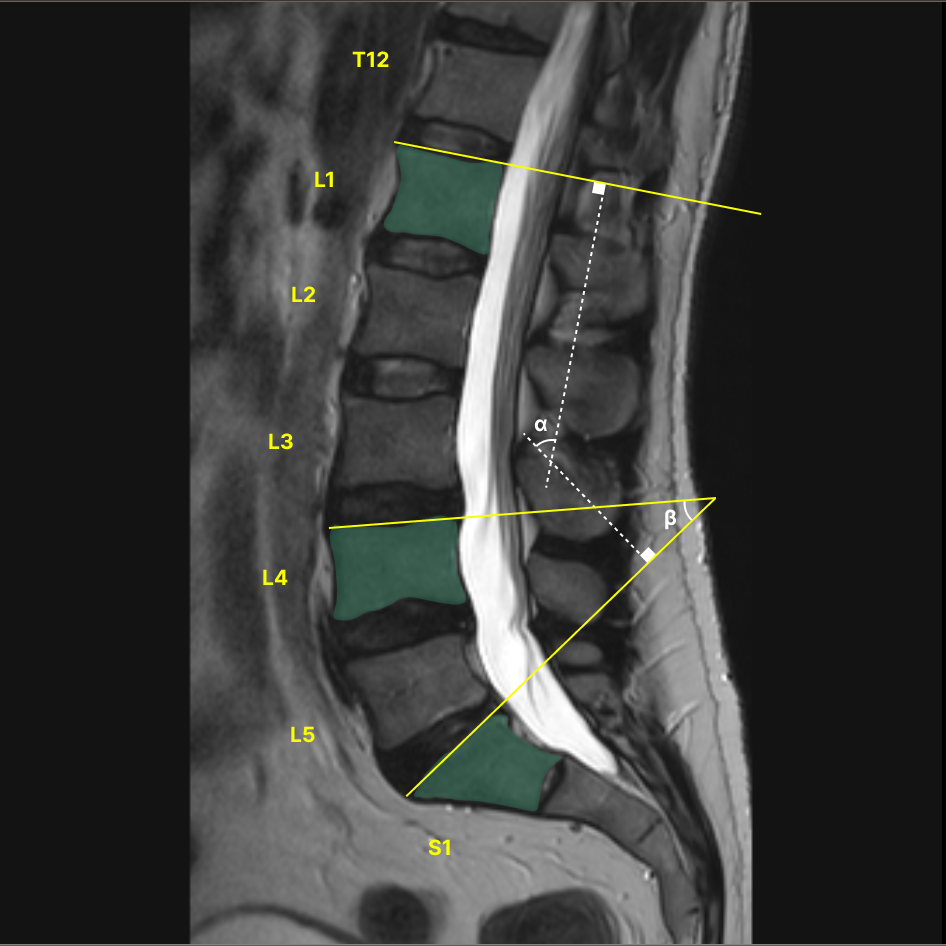

Designing and implementing three new sets of DICOM series (Summary, Sagittal, Axial) enhanced by AI to be viewed alongside original images, optimizing visual appeal and user experience through collaboration with physician consultants and detailed design systems, ultimately bridging the gap between machine learning outputs, customer requirements, and business goals.

I began by delving into various visual possibilities and experimenting with them alongside our physician consultants. Gathering feedback from these sessions, I collaborated with the team to refine and solidify the designs.

Throughout this process, I used my clinical expertise from supporting 1000s of cases and learning physician workflows. For instance, when presenting to the engineering team, I emphasized the technical aspects of the product’s implementation, using detailed schematics and mock-ups to illustrate feasibility and functionality.